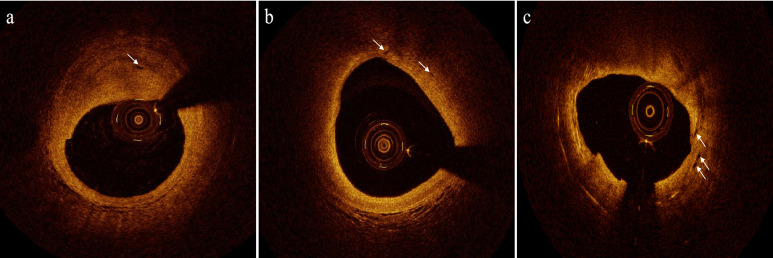

随着全球动脉粥样硬化性心血管疾病的增加,对有效识别导致动脉粥样硬化斑块破裂的高危因素和寻找新的治疗靶点的需求也在增加。斑块内新生血管的形成被广泛认为是斑块易感性的重要指标。因此,及时发现斑块内新生血管并进行早期干预治疗有助于减少斑块破裂引起的潜在不良心血管事件。本文介绍了新生动脉粥样硬化斑块的形成机制、临床意义、检测技术及预防策略。

Following the global increase in atherosclerotic cardiovascular diseases, the demand for the effective identification of high-risk factors that lead to atherosclerotic plaque rupture and the search for new therapeutic targets has also increased. Neovascularization within plaques is widely recognized as an important indicator of plaque vulnerability. Thus, the timely detection of neovascularization within plaques and early intervention treatment can help reduce the potential adverse cardiovascular events caused by plaque rupture. This article introduces the formation mechanism, clinical significance, detection techniques, and prevention strategies for neovascularizing atherosclerotic plaques.